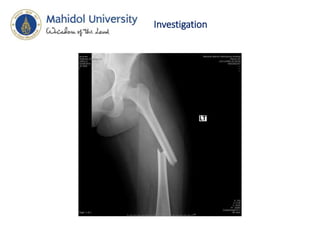

Investigation

• Film femur AP , lat

• Hip AP,lat

• Knee AP,lat

Diagnosis • Close fractureLt shaft of femur • Swelling of Lt knee